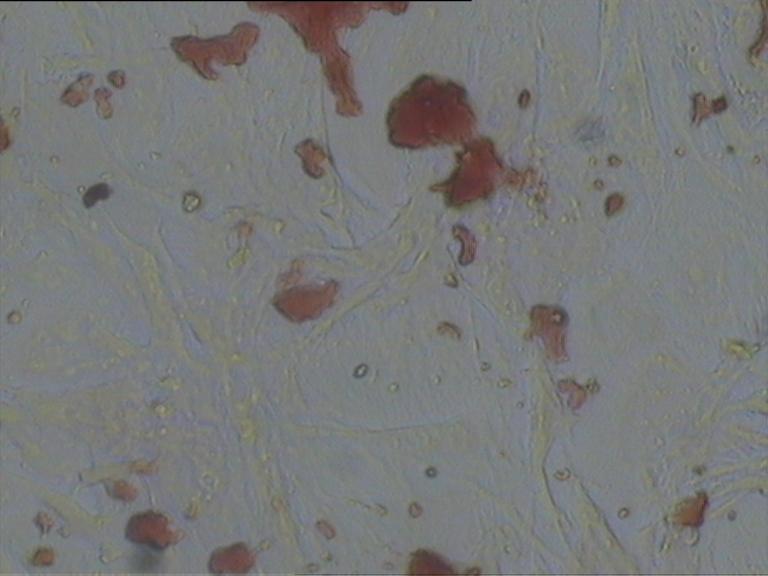

免疫組化染色

對照組

給藥組

模型組